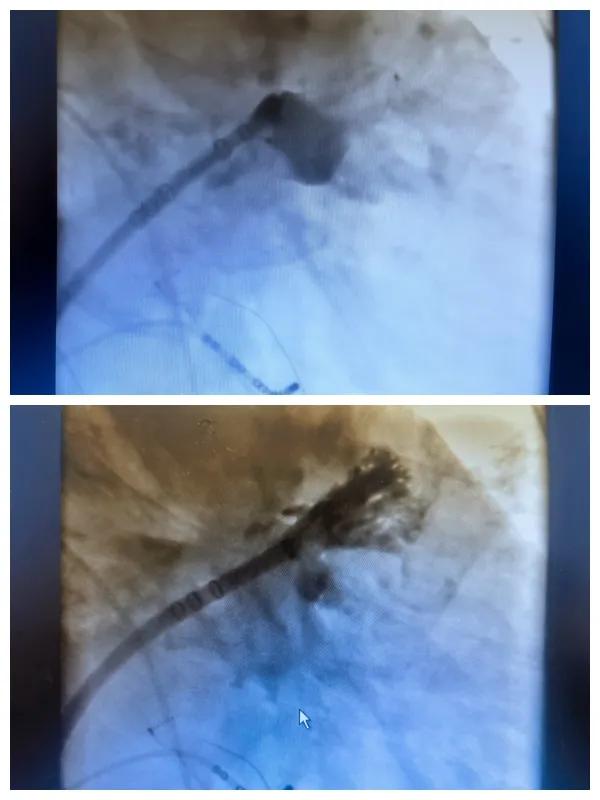

6月26日,市二院成功為一名老年房顫患者實(shí)施了房顫射頻消融術(shù)+左心耳封堵WM FLX一站式介入治療,標(biāo)志著醫(yī)院在心律失常介入治療領(lǐng)域邁出了嶄新的一步,開(kāi)啟了新的治療篇章。

本次手術(shù)特邀我國(guó)著名心血管內(nèi)科專家、河南省胸科醫(yī)院黨委書(shū)記袁義強(qiáng)及血管內(nèi)科七病區(qū)主任黃瓊教授蒞臨指導(dǎo),市二院院長(zhǎng)王瑾帶領(lǐng)心血管內(nèi)科電生理等專家團(tuán)隊(duì)緊密合作,一次性解決了患者房顫、血栓兩大困擾,也使患者告別了終身服用抗凝藥的痛苦,極大地降低了患者的經(jīng)濟(jì)和用藥負(fù)擔(dān)。

為了讓患者得到全面、綜合的治療,經(jīng)過(guò)團(tuán)隊(duì)術(shù)前充分討論,并征得家屬同意,心血管內(nèi)科團(tuán)隊(duì)決定采用目前國(guó)內(nèi)外先進(jìn)的房顫射頻消融術(shù)+左心耳封堵WM FLX一站式介入微創(chuàng)手術(shù)來(lái)治療老人的疾病。整個(gè)手術(shù)過(guò)程圓滿順利,術(shù)后何大爺各項(xiàng)體征正常,蘇醒后順利返回病房。